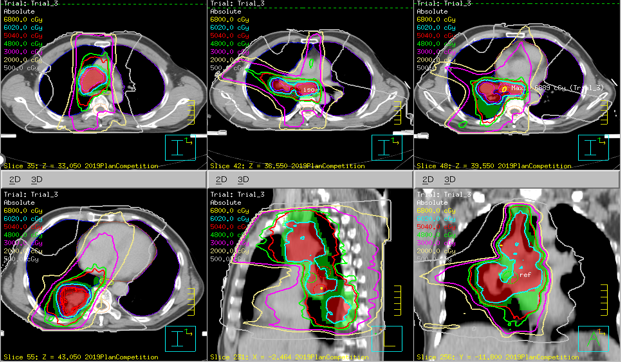

Winning Plans

Winners – TPS : Eclipse

Winners – TPS : Monaco

Winners – TPS : Pinnacle

Winners – TPS : RayStation

Winners – TPS : Tomotherapy

Case : Locally advanced non-small cell lung cancer

Dose Prescription:

95% PGTV 60.2 Gy/2.15 Gy/28 F

95% PTV 50.4 Gy/1.8 Gy/28 F

Protocol : RTOG0617

Techniques : IMRT/VMAT/HT